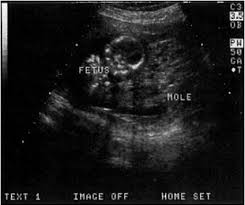

What are the chances of having twins? When six full weeks have passed (after week 6+0) you should be able to detect all kinds of twins using ultrasound. A full bladder provides an ultrasonic window to better see what's inside the uterus. I've been posting in october 2012 since i found out i was pregnant in february. 6 weeks 4 days pregnant progress check in the 7th week of pregnancy, your baby's lungs are starting to develop. They confirmed the presence of a gestational sac, yolk sac and fetal dipole, but could not detect a heartbeat. Between 5 ½ to 6 ½ weeks, a fetal pole or even a fetal heartbeat may be detected by vaginal ultrasound. The fetal pole is the first visible sign of a developing embryo.

The exact time twins can be detected depends on the type of twins, for example, if they're identical (from one egg) or not. By eight weeks of your twin pregnancy, your babies will have buds for limbs that look like little paddles. Mehr als 200.000 maschinen sofort verfügbar. Most doctors will schedule an ultrasound somewhere between 6 and 10 weeks of pregnancy to confirm the pregnancy and check for multiples. Six full weeks is when you're 6+0 weeks pregnant. I should be 7 weeks, 4 days according to last period. (florida) i suspected i had twins because my beta numbers were high, i had two big follicles during my iui and i'm already big for less than 7 weeks! Seeing twins at 6 weeks is definitely possible. Besides ultrasound at 4 weeks, there are several changes during pregnancy for moms to expect. By four weeks, twins will start showing during ultrasound in form of 2 gestational sacs, but you cannot get clear indication of twins until 6 weeks. The first time i spotted but the other two were gushes. This was taken at 4 weeks 6 days. Some women would rather not know until both twins are relatively safe, while others want to know even if the chances of losing one twin are high.